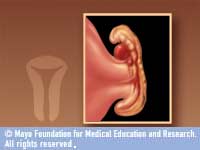

HÁROM HÉTTEL A FOGANTATÁS UTÁN KIALAKUL A SZÍV

HÁROM HÉTTEL A FOGANTATÁS UTÁN KIALAKUL A SZÍV